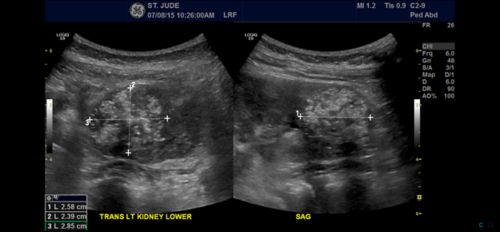

Atypical Teratoid Rhabdoid Tumor At Rt In Children Together

together.stjude.org